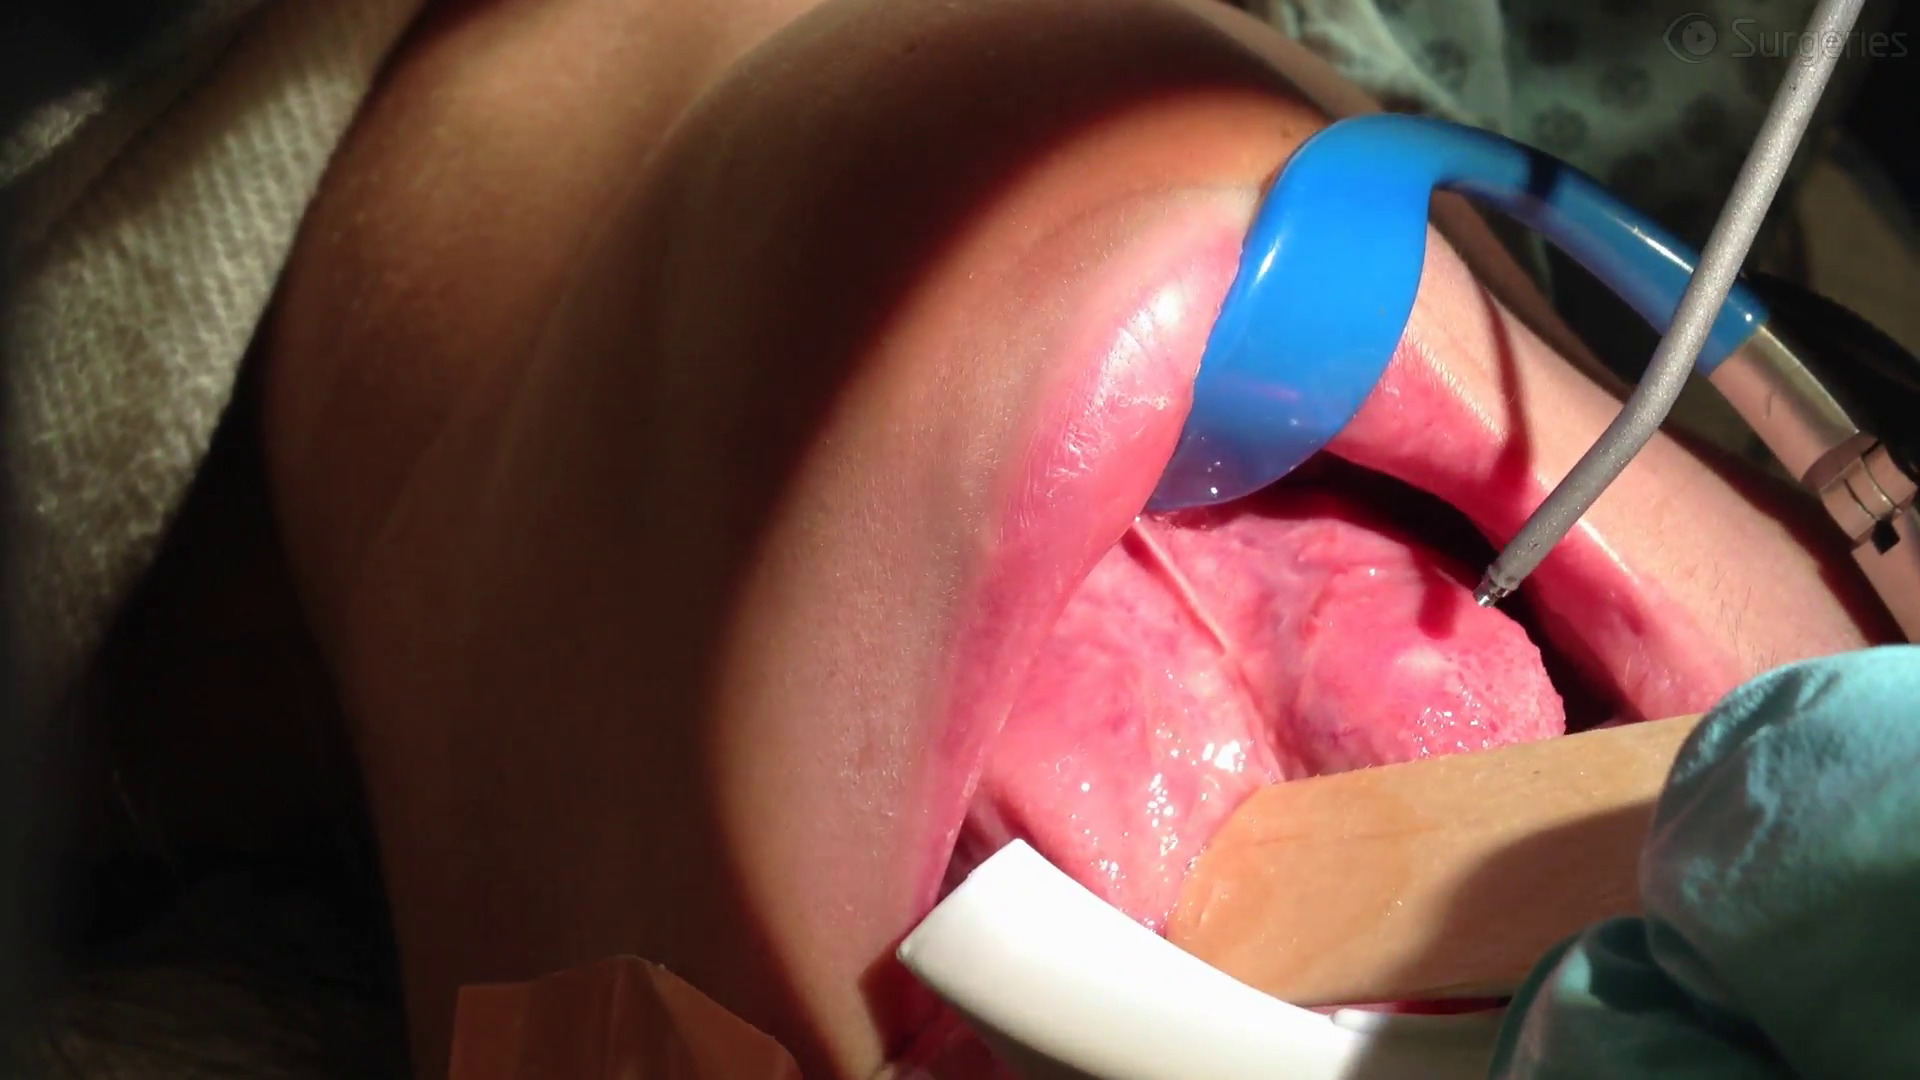

Watch the Full VideoThis video demonstrates a myringoplasty procedure using Neox RT - a human birth tissue allograft - to repair a tympanic membrane perforation in a pediatric patient. Neox RT is indicated as a wound covering for dermal ulcers or defects, but it holds further utility for myringoplasty. Birth tissue contains growth factors that stimulate epithelialization, as well as extracellular proteins that furnish scaffolding material for wound repair. These properties make it a natural and appealing option to induce tympanic membrane regeneration and healing.

We employ a “sandwich” technique, in which pieces of the allograft are placed both medial and lateral to the perforation. Simple overlay and underlay techniques have been tried with success, but the allograft is packaged as a single piece that affords enough material to craft two smaller pieces. The simultaneous placement of medial and lateral grafts not only avoids waste but may increase success.

Both pieces are trimmed to be slightly larger than the perforation. After freshening the edges of the perforation with a Rosen pick and partially filling the middle ear with dry, absorbable gelatin sponge, trimmed pieces of allograft are inserted sequentially in underlay and overlay fashion to remain medial and lateral to the perforation. Both the underlay and overlay pieces cover the perforation and overlap the native tympanic membrane around the perforation. More absorbable sponge is then inserted lateral to the graft to hold it in place against the tympanic membrane. Finally, antibiotic drops and bacitracin ointment are placed in the canal.